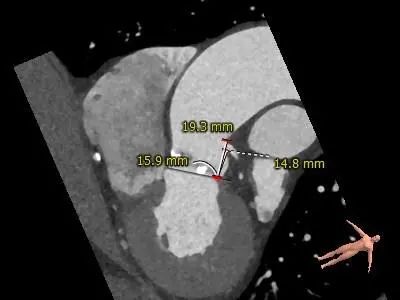

主动脉根部评估

CT 数据显示该患者为Type1型二叶式主动脉瓣

主动脉瓣瓣环周长72.5mm,周长径23.1mm

LVOT 周长 85.1mm,周长径27.1mm

SOV:31.1mm*33.6mm*31.6mm

STJ 周长 91.9mm

无冠瓣钙化严重,HU850:448mm³

瓣环水平夹角46度